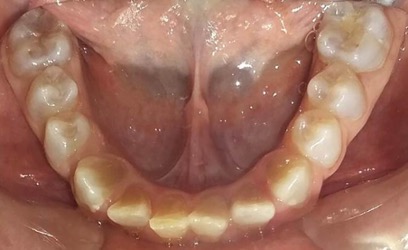

En la radiografía panorámica de control del año 2015 se observó la progresiva obliteración del conducto radicular en el grupo incisivo superior e inferior y en los primeros molares permanentes; presentado los premolares en erupción, un conducto radicular anormalmente amplio en toda su longitud (Figura 8). En la del año 2018 se visualizó la continua aposición de dentina a nivel radicular que obliteró en forma casi total los conductos de la mayoría de las piezas dentarias, a excepción de los segundos molares inferiores (Figura 10).

En el último control realizado en el año 2018 (Figura 11) el paciente mantuvo el estado de salud logrado. El análisis cariogénico fue moderado (por su historia pasada de caries y su condición biológica específica) y el gingivoperiodontal bajo. El paciente continúa en atención en la COIN. Fue derivado en varias oportunidades al servicio de Ortodoncia de la Facultad de Odontología de la Universidad de Buenos Aires, pero hasta el momento no encaró ningún tratamiento propuesto.